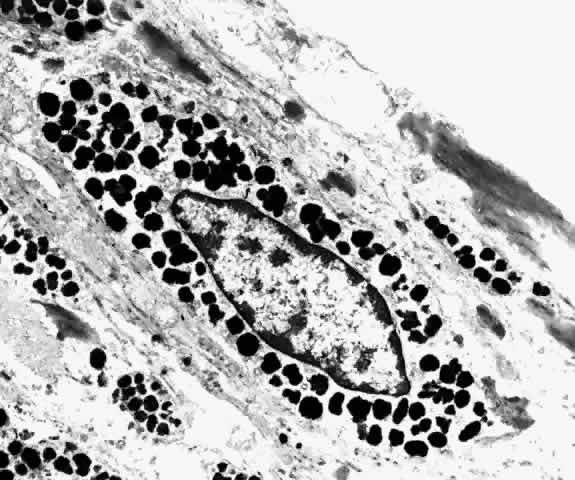

Bruch's membrane, also called the lamina vitrea, is the inner layer of the choroid. This thin, acellular, well-delineated zone between the retina and choroid extends from the optic nerve to the ora serrata. Composed of elements from both the retina and the choroid, Bruch's membrane is an integral part of the choroid. From internal to external, the membrane is formed of five layers: the basement membrane of the RPE, the inner collagenous zone, the elastic tissue layer, the outer collagenous zone, and the basement membrane of the choriocapillaris (Fig. 8).

Fig. 8. Bruch's membrane. Basement membrane of retinal pigment epithelium (rbm), inner collagenous zone (ic), elastic tissue layer (etl), outer collagenous zone (oc) and basement membrane of choriocapillaris (cbm). (× 14,500)

Bruch's membrane is thickest near the optic disc, measuring 2 to 4 μm, and gradually decreases in thickness to 1 to 2 μm peripherally.16 The innermost layer, the basement membrane of the RPE, is a continuous membrane measuring 0.3 μm thick. The outer layer, the basement membrane of the choriocapillaris, is 0.14 μm thick and is discontinuous at the intercapillary septa. The inner and outer collagenous layers are continuous and measure 1.5 μm and 0.14 μm, respectively. The middle elastic tissue layer is discontinuous. Normally, the layers of Bruch's membrane are so closely interwoven that they cannot be separated in a healthy globe.17–20